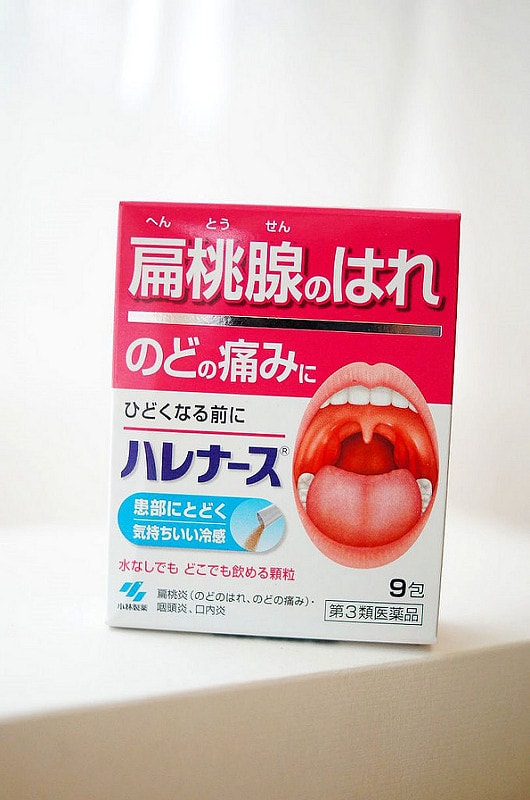

這沒吃過,是隨便抓的哈哈